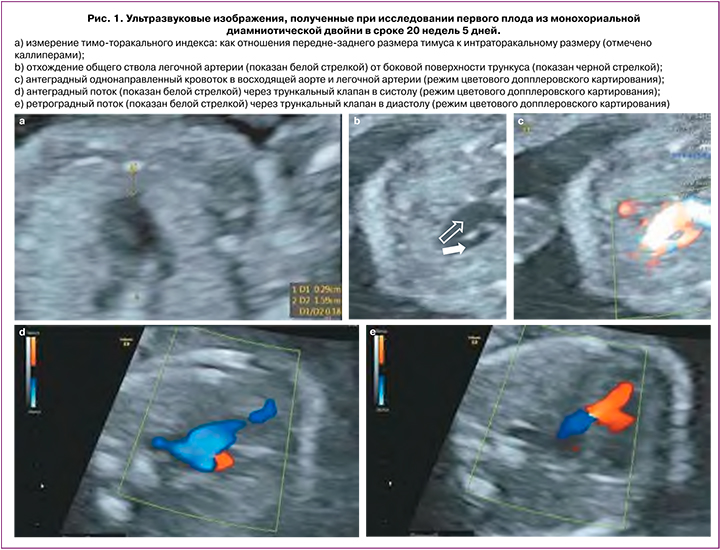

При проведении эхокардиографии у обоих плодов определялась аналогичная эхографическая картина: неизмененное положение органов брюшной полости и грудной клетки (situs solitus), нормальные размеры сердца, отклонение оси сердца влево более чем на 75 градусов. Четырехкамерная проекция была не изменена, определялись нормальное венозно-атриальное и конкордантное предсердно-желудочковое соединение, размеры и положение предсердий и желудочков соответствовали гестационной норме. Проекция выходных трактов левого/правого желудочков была аномальной. Определялся единственный артериальный сосуд (трункус – ОАС) с бивентрикулярным отхождением за счет наличия подтрункального дефекта межжелудочковой перегородки, отхождение ствола легочной артерии от боковой стенки трункуса (рис. 1) с последующим делением его на правую и левую легочные артерии. При цветовой допплерографии определялась выраженная недостаточность трункального клапана, антеградный кровоток в легочной артерии (рис. 1). Проекция трех сосудов и трахеи также была аномальной – вместо трех сосудов визуализировались только два: нормального диаметра верхняя полая вена и сосуд большего диаметра – трункус. Типичного V-соединения сосудов получить не удалось. Артериальный проток не визуализировался в типичном месте. Сагиттальный срез дуги аорты был не изменен – нормального диаметра брахиоцефальные сосуды отходили от дуги аорты с нормальным типом ветвления. ТТО было уменьшено до 0,18 у первого и до 0,21 – у второго плода (рис. 1). Признаков патологии со стороны других органов и структур обоих плодов не было выявлено.

Окончательный пренатальный диагноз был сформулирован следующим образом: Многоплодная беременность сроком 20 недель 5 дней с учетом даты первого дня последнего менструального цикла: монохориальная диамниотическая двойня. ВПС у обоих плодов: ОАС I типа по классификации Van Praagh. Уменьшение ТТО у обоих плодов. Высокий риск синдромальной патологии плодов (включая синдром делеции хромосомы 22).